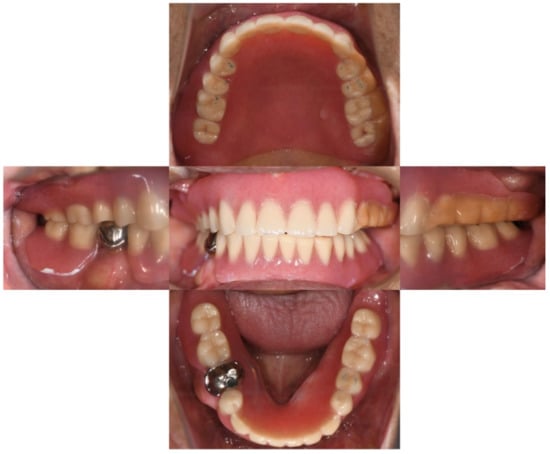

Intra-oral examination revealed maxillary total edentulism and mandibular partial edentulism with only the lower right second premolar remaining (Figure 1). The bony prominence around the bilateral tuberosity areas significantly reduced the space of the retrozygomatic fold. The bony prominence around the mandible extended from the lingual frenum to the retromylohyoid fossa bilaterally (Figure 2). Mild bony prominence was also present around the labial aspects of the maxilla and mandible, making it difficult to distinguish the peripheral frenula.

Figure 1. Intra-oral examination. The maxilla was completely edentulous. The mandible had only the lower right second premolar remaining.